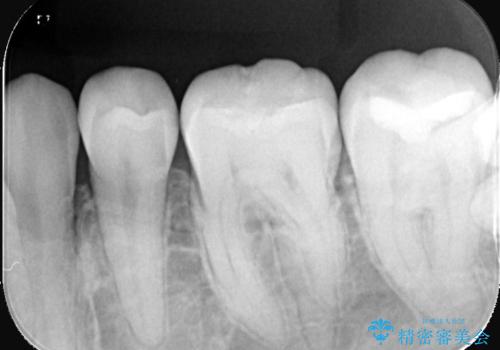

過去に虫歯の治療を受けた歯の噛む面に充填されているプラスチック材料が劣化し、歯質とプラスチック材料との境目に生じたギャップに汚れが溜まっている状態だったため、物性の安定したセラミックインレーにてやり替えとなりました。

充填されているプラスチックの材料を除去したところ、う蝕が広がっていたため除去しCR裏層の後セラミックインレー修復をしています。セラミックインレーセット時は、ラバーダム防湿を行っています。